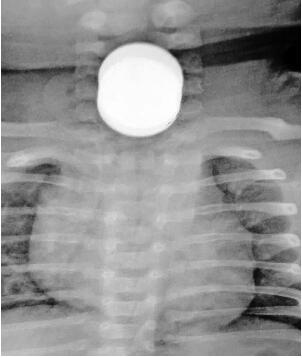

4月5日晚上7点,南京儿童医院急诊室,从宿迁紧急转运过来一名才两个月大的男宝宝。父母发现孩子总是吐奶,神情也焦躁不安,搞不清什么状况。医生一拍胸片CT发现,食道里卡了硬币,只能看出来是重叠的硬币,看不清楚有几个。孩子的父母一拍大腿,想起来了,肯定是家里那个两岁大的大宝干的。

由于诊断明确,没多久,孩子就上了手术台。十几分钟后,经过全麻手术,通过食管镜,医生从二宝的食道里取出3个一角面值的硬币。南京儿童医院耳鼻喉科专家说,幸好是一角钱,再大一点的话,不排除会出现危险。